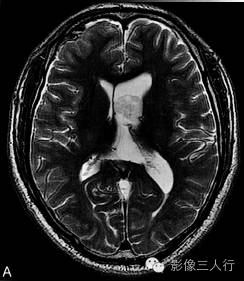

A.T2WI横断面;B.T1WI横断面;CFLAIR冠状面;D、E、F.增强横断面、矢状面、冠状面;G、H.CT平扫、增强;I.HE×100

肿瘤呈类圆形,边界清楚,位于左侧脑室前角及室间孔区,左侧脑室前角、三角部及左侧脑室后角扩张积水。MRI平扫T2WI(图A)肿瘤呈稍高信号,内见小范围高信号区;T1WI(图B)肿瘤呈等信号,内见低信号区;冠状面水抑制相(图C)肿瘤呈稍尚信号,内部原长T1长T2区信号呈低信号;增强扫描(图D~F)肿瘤强化不明显;CT平扫(图G)左侧脑室前角类圆形、边界清楚、较均匀等密度肿块,增强扫描(图H)强化不明显。